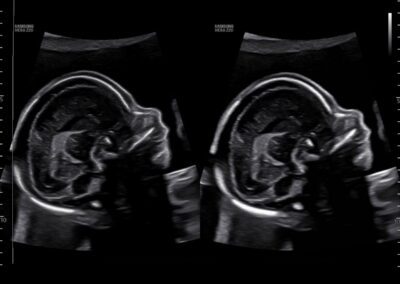

Complex Case Review / Second Opinion

For patients seeking additional clarity regarding prior ultrasounds, genetic testing, or specialist recommendations. Includes review of medical records and personalized recommendations.

Comprehensive, advanced and expert MFM care for high-risk pregnancies